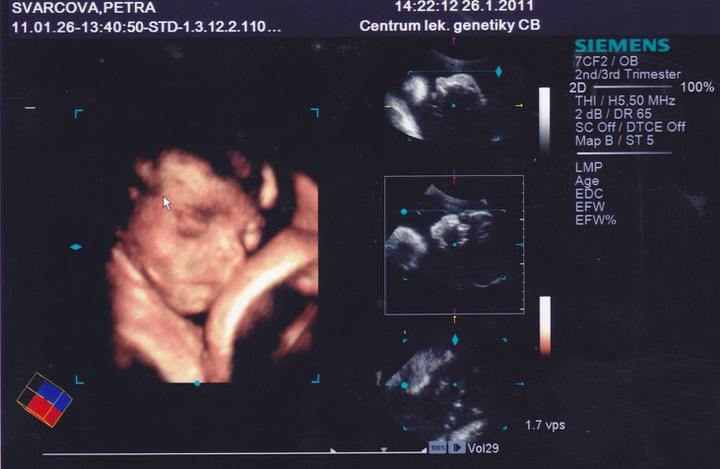

26.1.Jedu do Českých Budějovic na 4D ultrazvuk.Už se nemůžu dočkat.

Včera jsem Byla v Českých Budějovicíh.Jedno mimi váží 267g, a druhé váží 314g.A jsou to kluci.